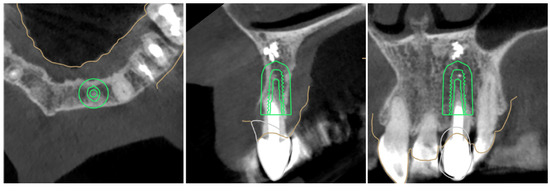

2.2. Surgical Protocol